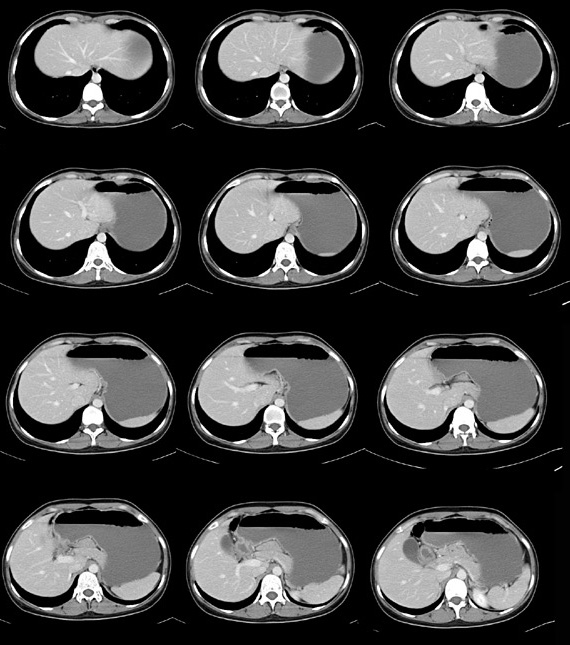

女性,28岁,停经3月,腹部膨隆1月,产前检查发现腹部占位

{肿块中心ct值27hu,增强后,动脉期、门脉期均无明显强化)

患者手术病理:腹腔囊性淋巴管瘤,象这样充满整个腹腔的的确很少见